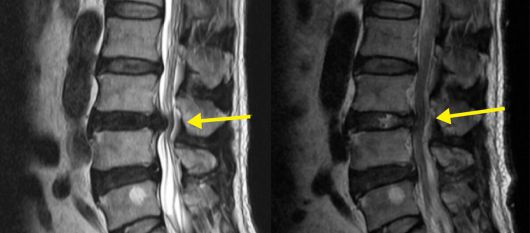

최근에는 절개 범위를 최소화한 최소침습 디스크 제거술이 널리 시행되고 있다. 이 수술은 피부 절개를 크게 하지 않고, 작은 통로를 통해 내시경이나 미세현미경을 삽입해 신경을 압박하는 디스크 조각만 선택적으로 제거하는 방식이다.

국소 또는 부분 마취로 진행되는 경우가 많아 전신마취 부담이 적고, 근육 손상을 최소화할 수 있다. 수술 과정은 영상 장비로 병변 위치를 정확히 확인한 뒤 1cm 내외의 절개를 통해 기구를 삽입하고, 신경과 탈출된 디스크를 구분해 문제가 되는 부분만 제거하는 순서로 진행된다.